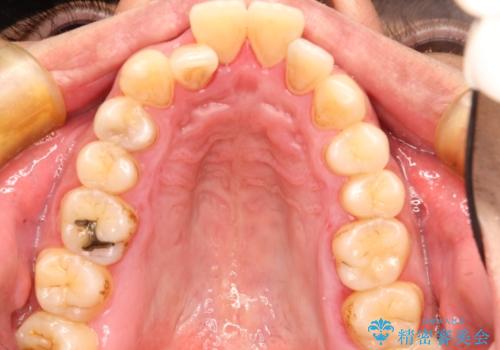

- 出っ歯が気になるとのことで来院されました。

上顎の前から4番目の歯を両側、合計2本抜歯して矯正する計画としました。

目立たない装置がご希望でしたので、上下裏側ワイヤー装置を選択されました。

裏側矯正は目立たないという利点がありますが、歯ブラシが非常に難しいなどのデメリットもあります。